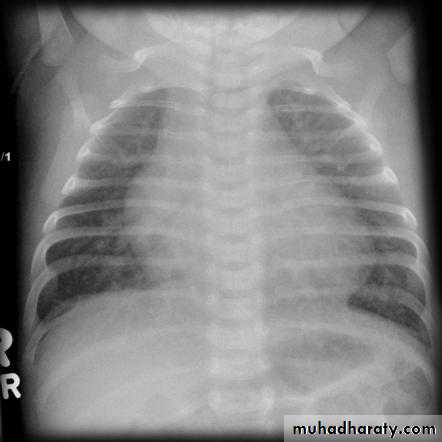

CXR: shows cardiomegaly, Rt atrial enlargement, prominent pulmonary artery and increased pulmonary

CXR: may be normal in small VSD, but in large VSD there is may be cardiomegaly and increased pulmonary vascularity.